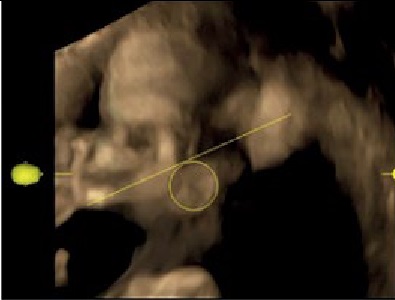

Возрастной период | Схема изменений топографических взаимоотношений ушной раковины плодов относительно нижней челюсти | Ультразвуковая сканограмма головы плода |

19–23 недели | Возраст 21 неделя, пол женский | |

Примечание. 1 – наружный затылочный выступ; 2 – гнатион; 3 – ушная раковина.

Методом ультразвукового сканирования можно изучить топографию, форму, структуры ушной раковины плода [13]. В исследовании использовались два режима: поверхностной реконструкции и костный (рисунок 1). Во всех случаях определяется условный центр ушной раковины. В костном режиме отчетливо визуализируются костные структуры, в режиме поверхностной реконструкции можно оценить форму ушной раковины и детали строения: завиток, противозавиток, козелок, противокозелок, мочку уха. Форма ушной раковины у плодов вариабельна (таблица 1).

Примечание. 1 – центральная часть ушной раковины; 2 – гнатион.

Рисунок 1. Ультразвуковая сканограмма головы плода. Возраст 20 недель, пол мужской. А – режим поверхностной реконструкции; Б – режим скелетный.

Figure 1. An ultrasound scan of the fetal head. 20 weeks old, male. A – a surface reconstruction mode; B – a skeletal mode.